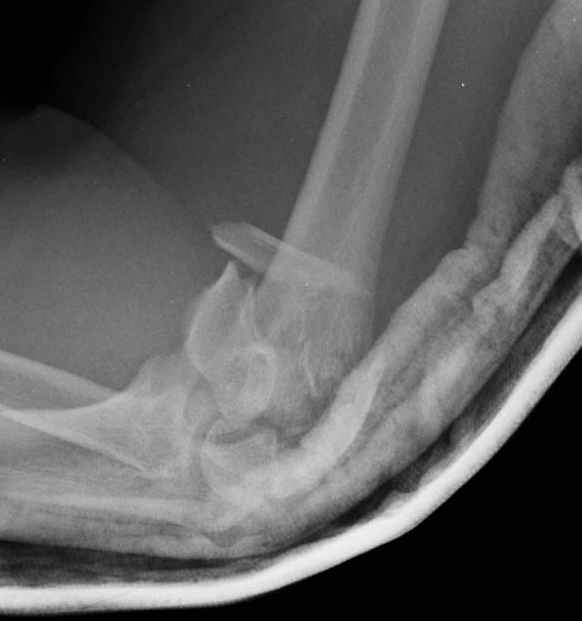

Djoldas Kuldjanov, M.D. 09 Сентябрь 2005, 20:07

Примерный случай, только перелом был открытый, в задне-медиальной стороне рана около 2 см по характеру "изнутри кнаружи", неврологический статус со слабостью сгибания мизинца, также слабая абдукция и аддукция указательного пальца и сгибания в кисти.

Больному сделали обработку и наложили временный аппарат внешной фиксации плечо-предплечье.

На шестой день сделали открытую репозицию чрезлоктевым доступом двумя locking plate, локтевой нерв был ушибленным, после операции положительная динамика в Flexor Carpi Ulnaris. Фиксацию локтевого отростка произвели tension band technique с дополнительным шурупом.

Этапы операции на снимках....